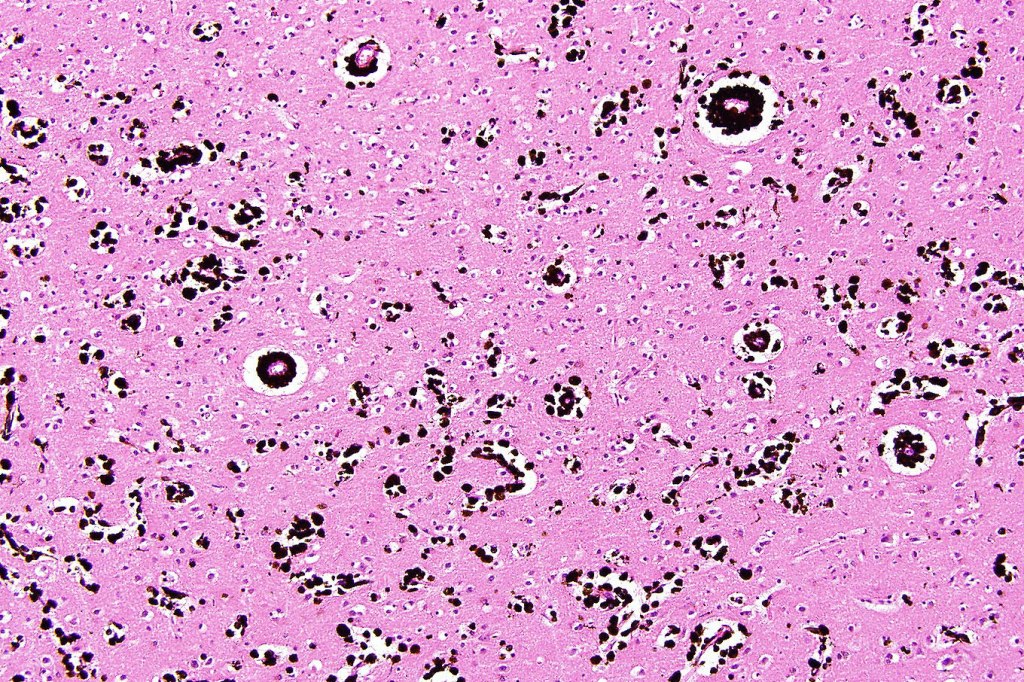

•Back lesions may be associated with leptomeningeal melanocytosis, spina bifida, intracranial melanoma & hydrocephalus (see below)

This melanoma arose in a small congenital nevus of the scalp. It metastasized widely. Varying features in different fields.